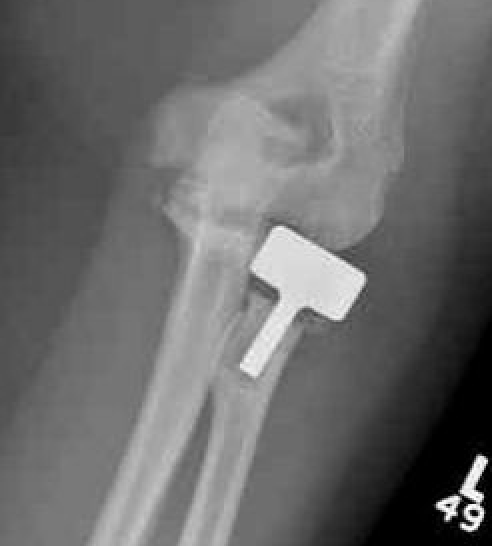

![]() |

Overstuffing

| Lesser sigmoid notch | Symmetry of ulnohumeral joint |

|---|---|

|

Radial head shoulder articulate with lesser notch

Ensure no gapping of lateral ulnohumeral joint |

- cadaveric study

- increased medial ulno-humeral joint line gapping with overlengthening of 6 or 8 mm

- increased lateral ulno-humeral joint line gapping with overlengthening of 2 mm